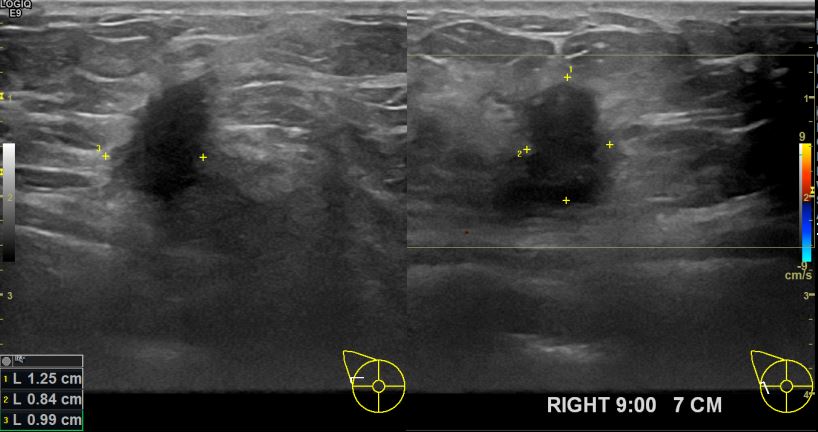

아산유외과 개원후 639번째 유방암진단

상기환자 외부검사상 이상소견으로 내원하신 40대여성으로 우측 유방의 의심스러혹

조직검사시행해 유방암 진단되었읍니다